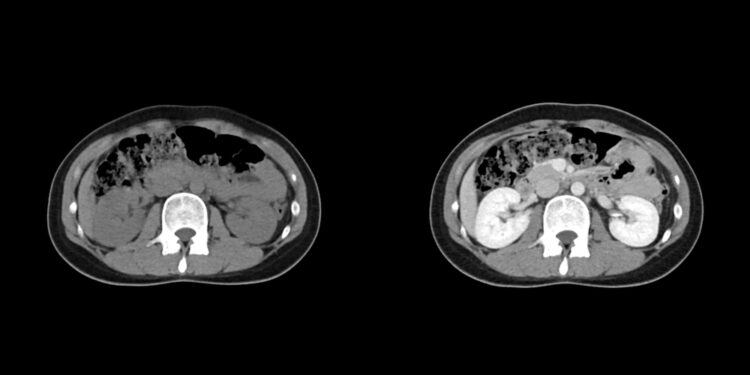

Dažnai į pagalbą pasitelkiami vaizdiniai tyrimai, pavyzdžiui, magnetinio rezonanso tomografija (MRT). Kai kada, norint tiksliai identifikuoti darinio kilmę, atliekama biopsija – paimamas naviko audinio mėginys. Šį mėginį patologoje ištyrę medikai nustato, ar navikas nepiktybinis, ar vis dėlto piktybinis.